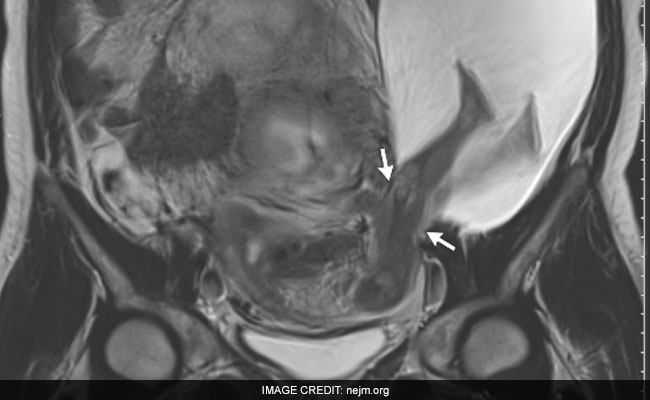

French Doctor Discovers Baby's Legs Protruding From Mother's Womb

When Pierre-Emmanuel Bouet discovered that his pregnant patient had pair of legs protruding into her side from her uterus - the organ in which entire fetuses traditionally gestate before they are born - the doctor was flabbergasted.